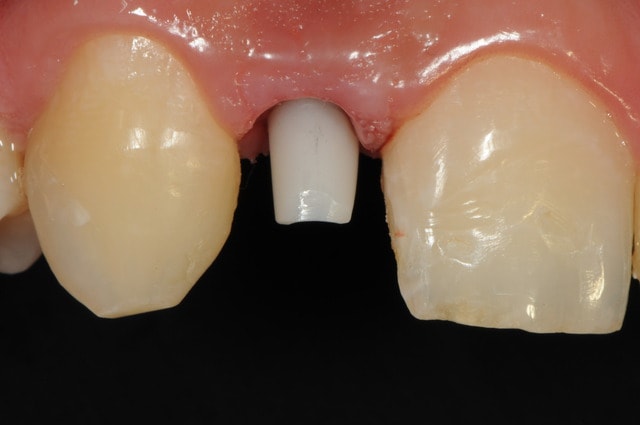

-cicatrisation de la première vis de cica,

-diamètre plus gros pour la vis de cica

- pilier pour la provisoire

- provisoire moule ION

- ajustage

- polissage soigneux

la suite tout à l'heure, ça sonne à la porte...